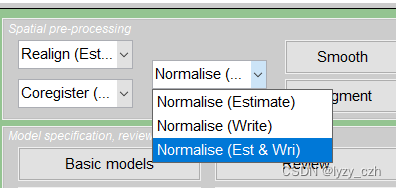

3)将mean002_s_0729的hdr数据配到PET模板上,点击Normalise(Est & Wri)